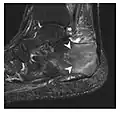

Figure 10: Calcaneal fatigue fracture in a 30-year-old male runner. Radiographs were normal (not shown). (a) Sagittal T1-weighted and (b) short tau inversion recovery images show a linear hypointensity (arrows) of calcaneal tuberosity within diffuse bone marrow edema, which appears as an ill-defined area of hyperintensity on a fluid sensitive pulse sequence (arrowheads).[1]

Figure 11: Stress fracture of the right radius in a 40-year-old man, a semiprofessional billiard player, with no history of trauma and complaining of pain of the right forearm for one month. (a) Anteroposterior radiograph shows medial radial cortex periosteal reaction (arrow) but no fracture line is seen. (b) Coronal reformatted CT depicts monocortical fracture line through the periosteal thickening (arrowheads). (c) Coronal T2-weighted fat-suppressed MRI shows intramedullary hyperintensity within the bone marrow (arrow) corresponding to bone marrow edema.[1]